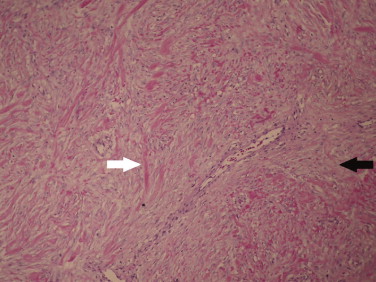

During the surgery, contrary to expectations, it was ascertained that inside the scrotum the patient had a healthy right testicle and spermatic cord together with an indirect inguinal hernia whose sac surrounded the large mass (Fig. 1 ).

Appearance of the structures inside the right scrotum of the patient during the ...

Figure 1.

Appearance of the structures inside the right scrotum of the patient during the surgery; inside the right scrotum the patient had a healthy right testicle (thin white arrow) and spermatic cord together with an indirect inguinal hernia which sac (thin black arrow) was surrounding the big mass (thick black arrow); this mass was linked to the epiploon and splanchnic/mesenteric circulation (thick white arrow).

The mass inside the herniary sac was completely separated from it and only fixed to a small portion of the omentum and vessels; this portion was ligated, the mass was completely removed and the indirect inguinal hernia was corrected.